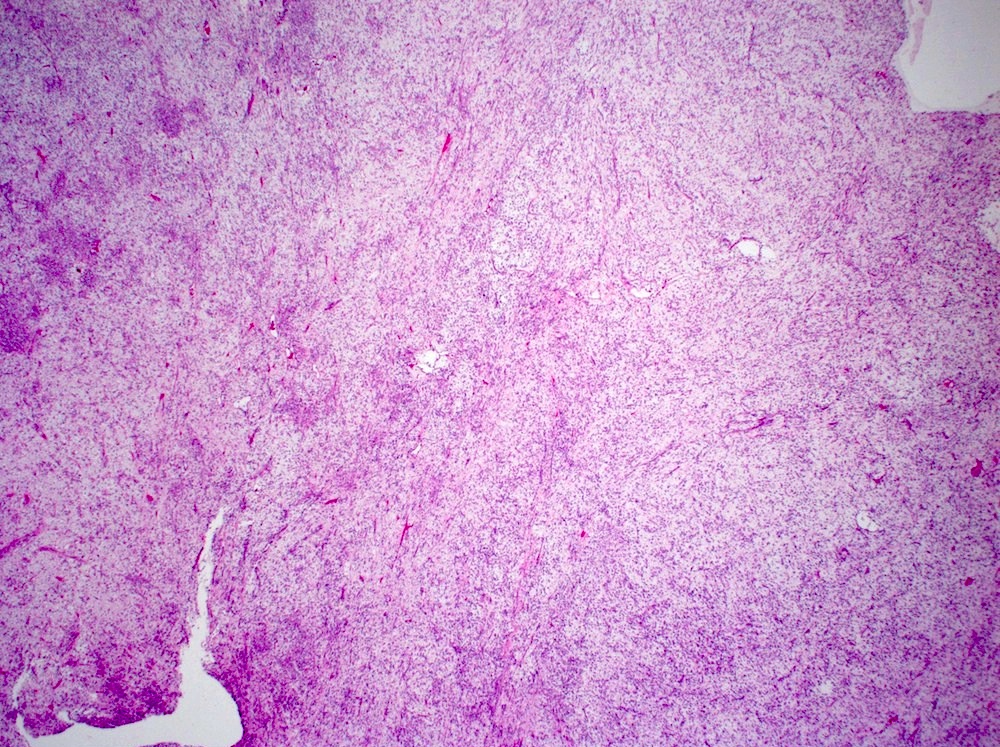

Microscopic (histologic) description

- Bland spindle cells with abundant amphophilic cytoplasm and variably prominent nucleoli

- Lymphoplasmacytic infiltrate with polyclonal plasma cells

- Background may show myxoid change or laminated / whorled fibrosis

- Epithelioid inflammatory myofibroblastic sarcoma: similar, except cells are more epithelioid, with large nucleoli

Microscopic (histologic) images

Contributed by Raul S. Gonzalez, M.D.